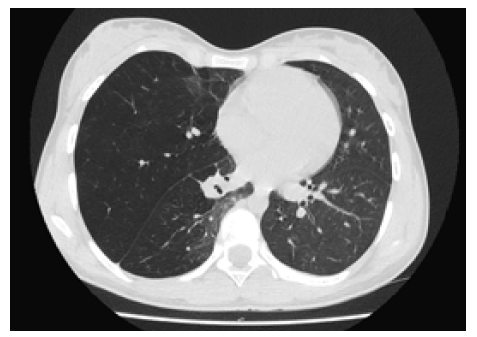

При КТ с внутривенным контрастированием от 06.04.2018 в верхней и нижней долях правого легкого были выявлены участки уплотнения легочной ткани по типу «матового стекла», фиброзные тяжи и спайки в правой плевральной полости, средняя доля находилась в состоянии гиперинфляции, средостение смещено в сторону левого легкого (рис. 1). При этом верхне- и нижнедолевые бронхи правого легкого были отечны и несколько деформированы. Левое легкое без видимой патологии. При сцинтиграфии от 05.04.2018 было обнаружено резкое снижение накопления радиофарм препарата во всех долях правого легкого, подтверждающее дефицит перфузии (рис. 2). При бронхоскопии, выполненной 09.04.2018, выявлено, что устье правого среднедолевого бронха имеет щелевидную форму: было сделано заключение о пороке развития правого легкого. При ультразвуковом исследовании брюшной полости патологии не обнаружено.

Рис. 2. Аксиальный скан КТ ОГК гиперинфляция средней доли правого легкого, частичная компрессия нижней доли, смещение средостения влево